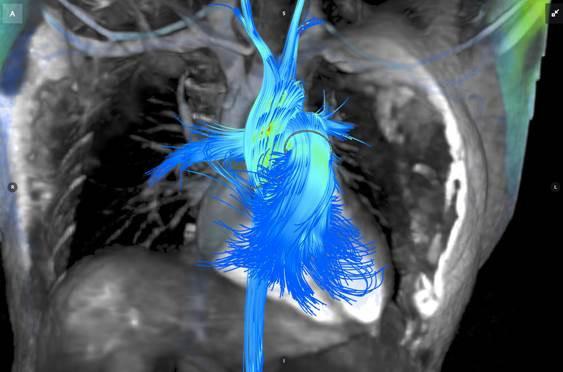

Advances in healthcare practice and technology are largely driven by research, and in recent years perhaps no discipline has been more influential than informatics — the study and practice of creating, storing, finding, sharing and manipulating information. More efficient storage and sharing of medical data are crucial in the transition to value-based healthcare, and radiology plays a central role in these efforts. Several major studies published in 2016 examined the role of informatics technology in medical imaging, and many of those studies were highlighted in a session at the 102nd annual meeting of the Radiological Society of North America (RSNA), Nov. 27-Dec. 2, 2016, in Chicago.